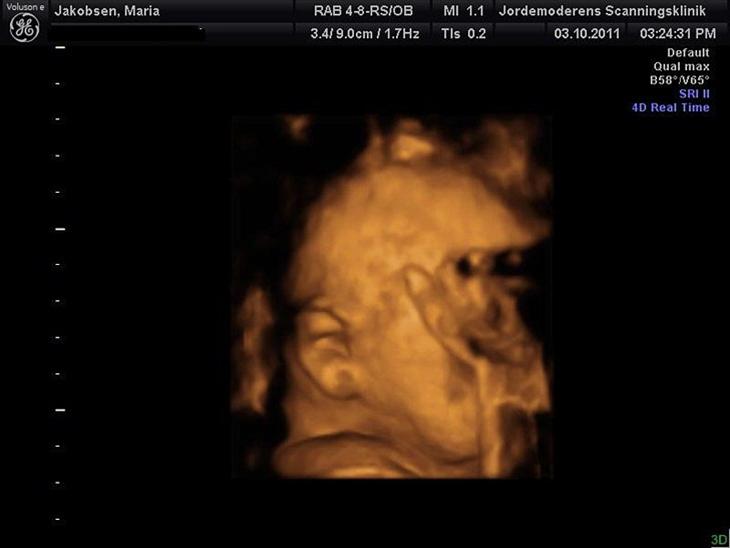

Vi var til 3D/4D scanning igår (Uge 31+1) og vi fik en masse gode billeder af babydrengen som jeg gerne vil vise frem :O)

Han vejer 2016gr , så han er lidt over gennemsnittet :O)